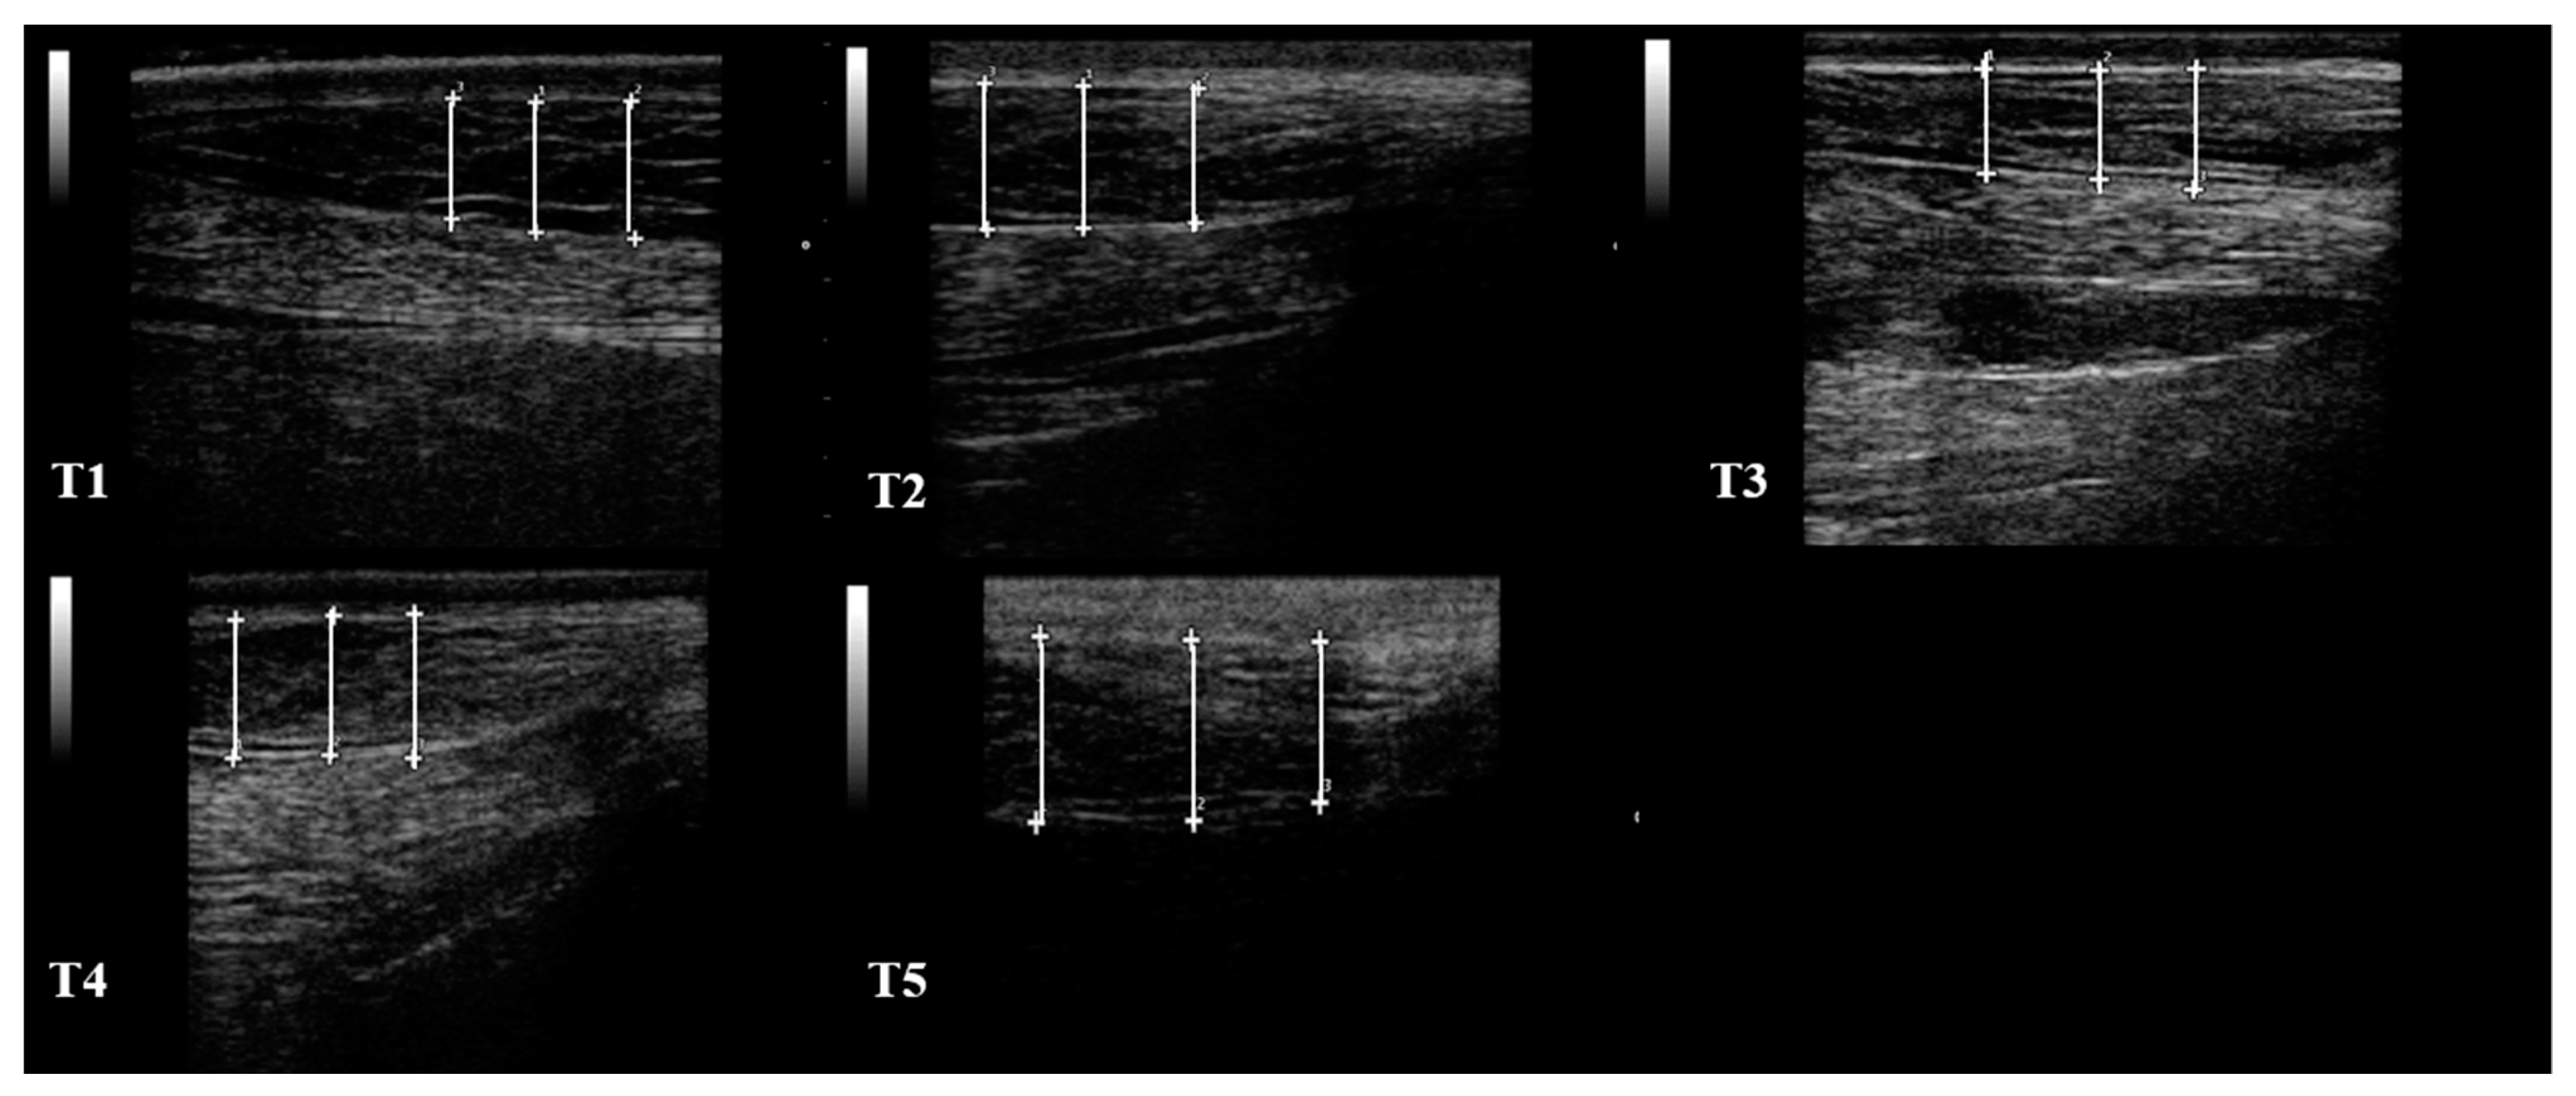

| S1 (mm) | 10.95 ± 3.12 | 12.03 ± 3.09 | 10.87 ± 3.01 | 12.32 ± 1.75 | 10.72 ± 1.29 | |

| S2 (mm) | 3.60 ± 0.86 | 4.23 ± 1.18 | 3.50 ± 1.18 | 2.85 ± 0.64 | 2.12 ± 0.41 | |

| S3 (mm) | 9.17 ± 7.17 | 7.30 ± 3.10 | 7.47 ± 2.96 | 6.90 ± 3.37 | 5.92 ± 3.10 | |

| S4 (mm) | 11.70 ± 1.37 | 12.45 ± 1.23 | 14.90 ± 1.75 | 15.80 ± 2.40 | 15.35 ± 1.73 | |